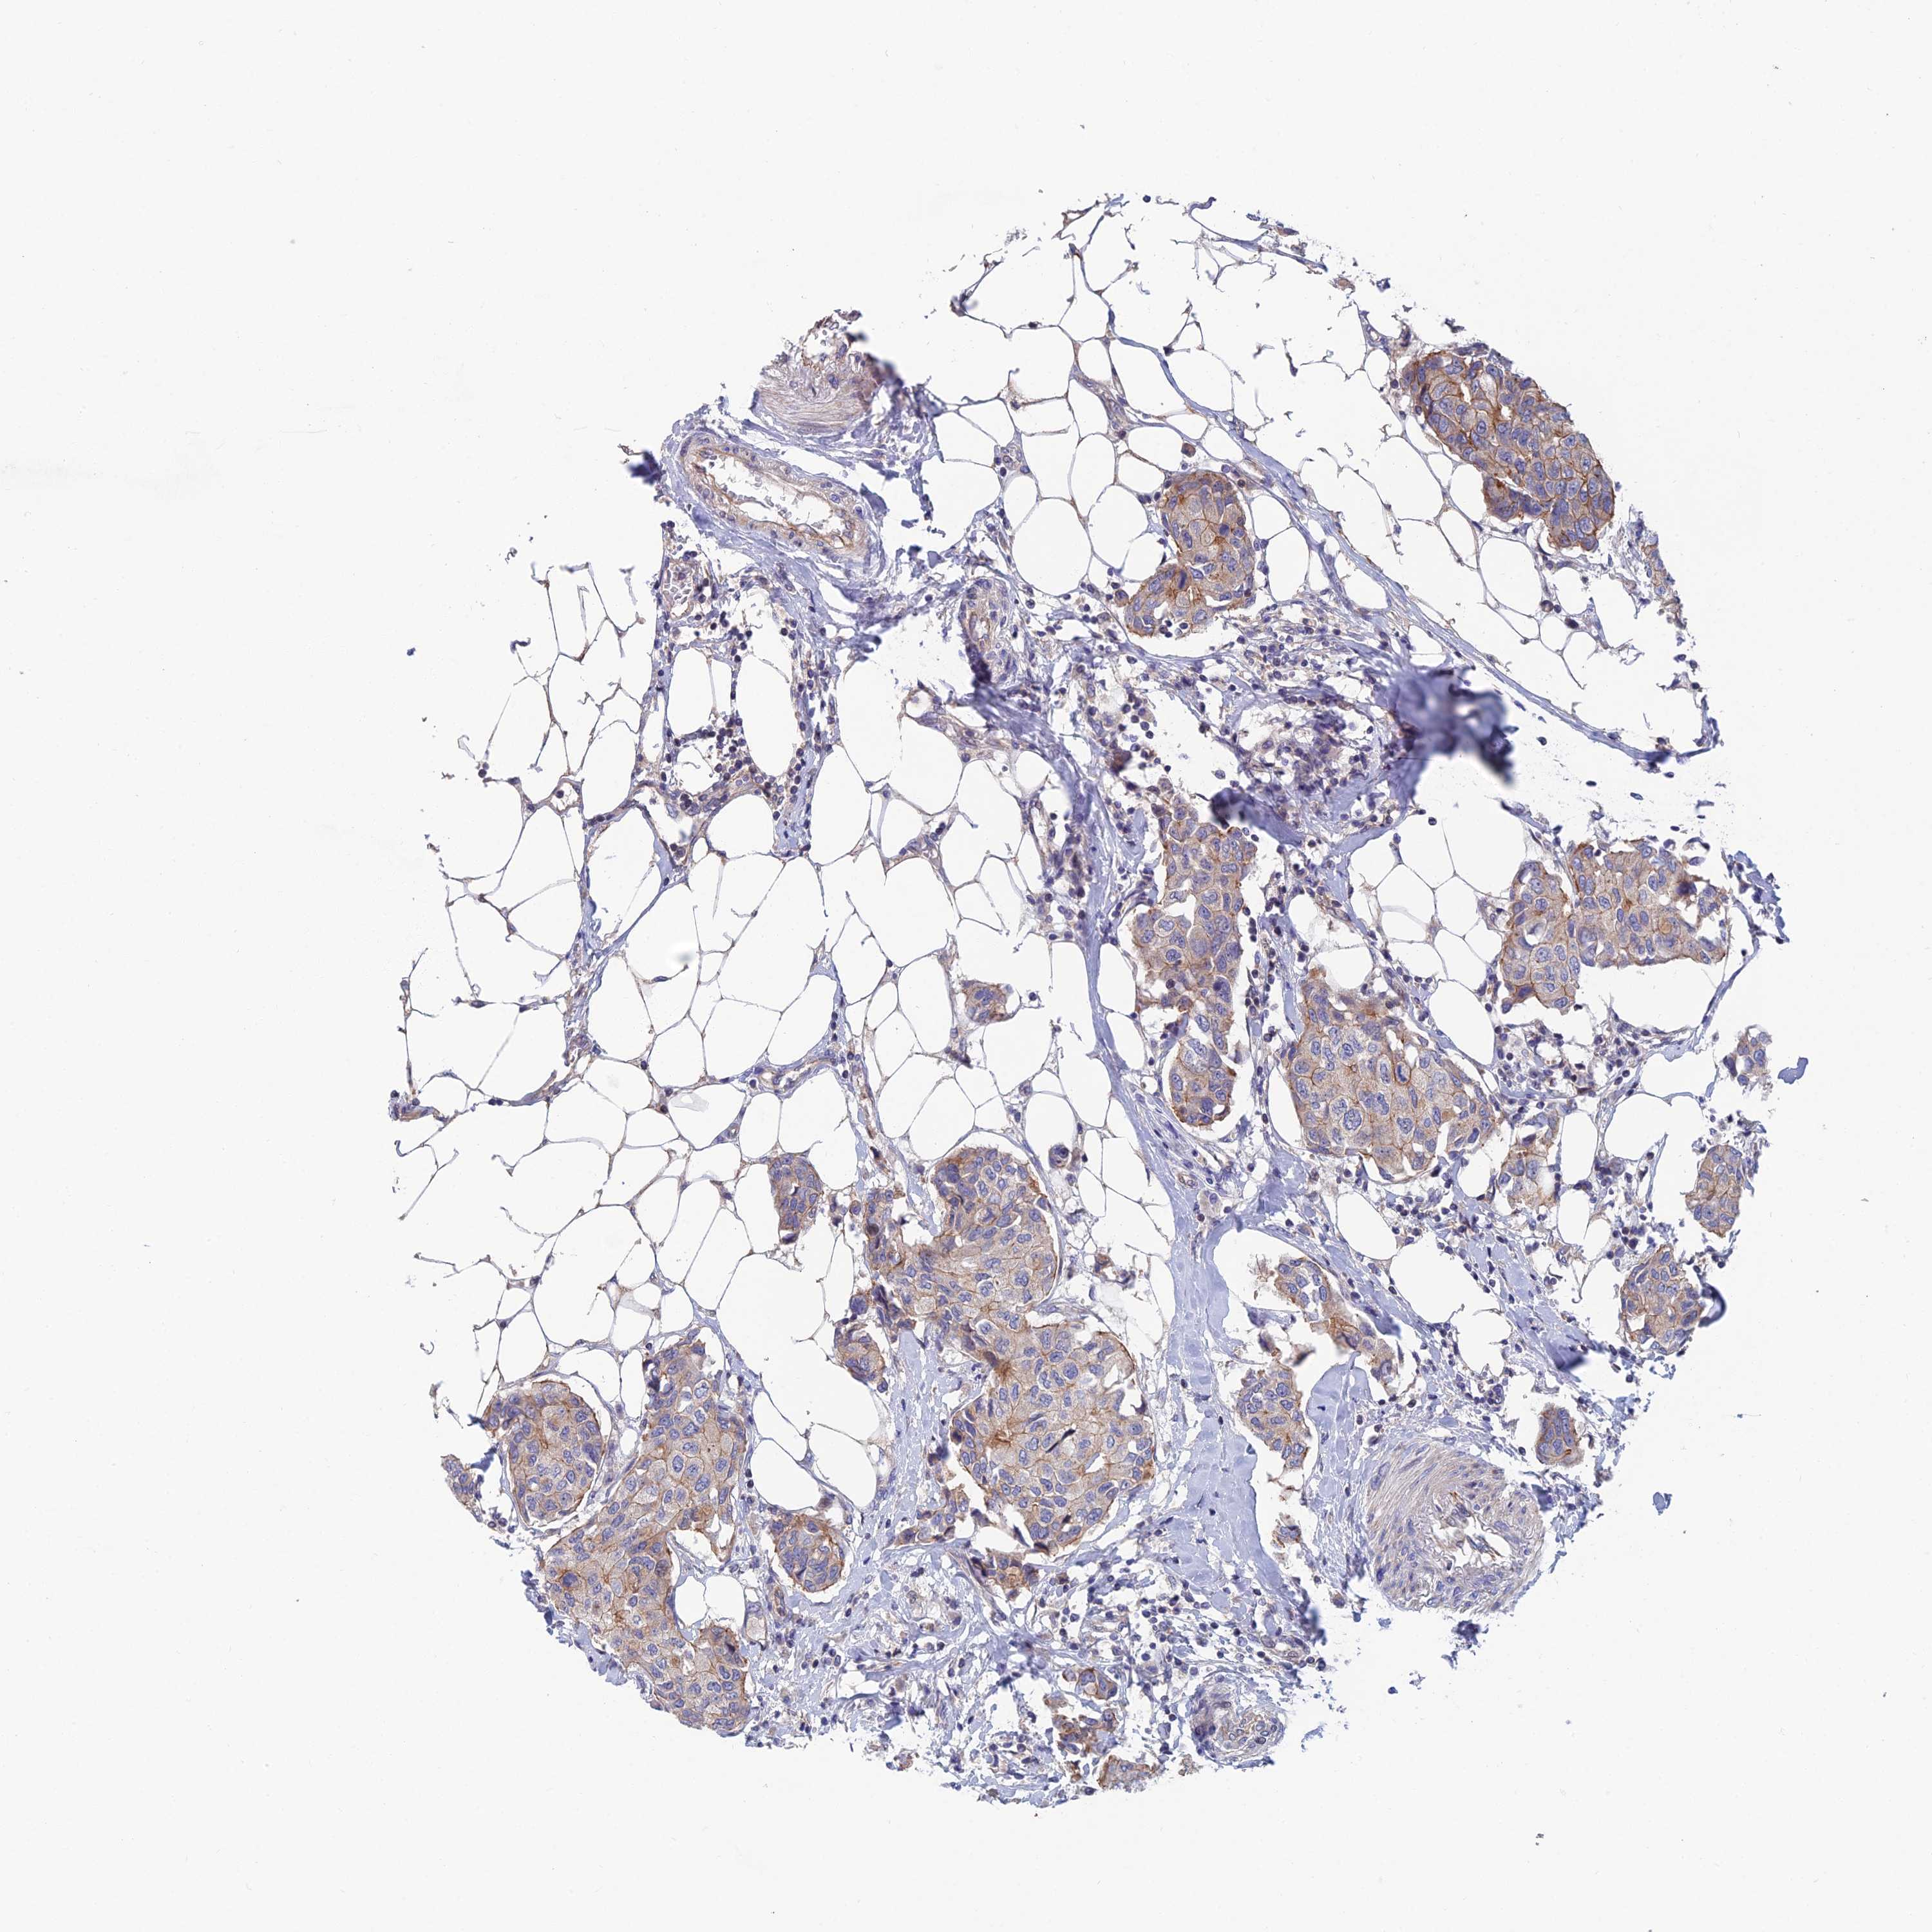

BRCA TCGA BRCA VALIDATION PROTEIN EXPRESSION